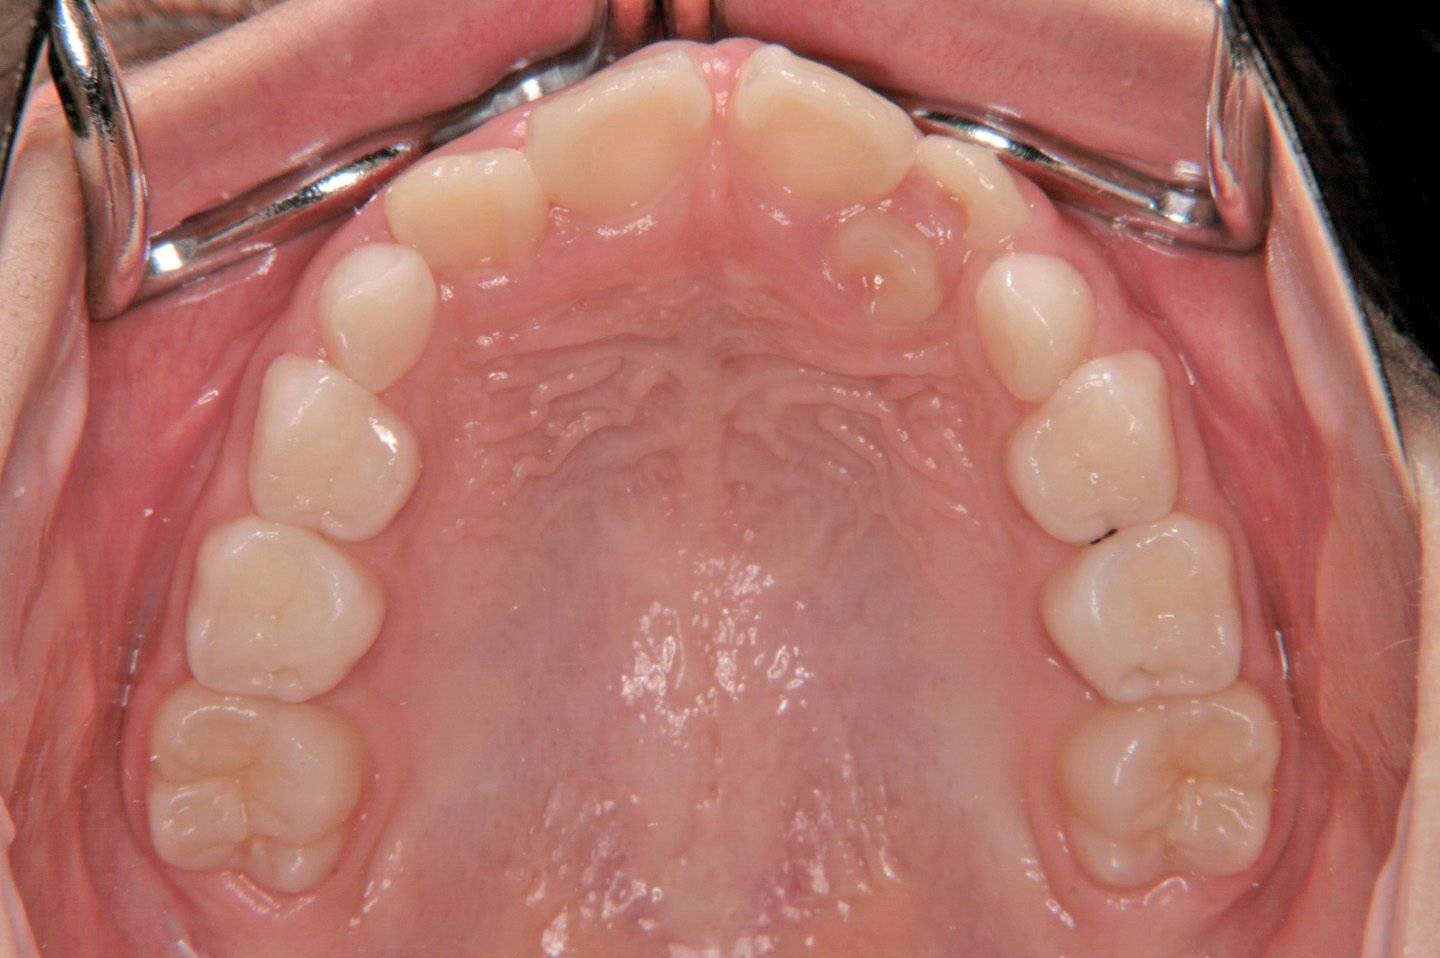

上顎前突(出っ歯)

叢生(乱ぐい歯)

過剰歯

前歯のデコボコを気にされて来院された7歳の女子です。検査の結果、上顎前突で上下顎ともに歯の並ぶスペースが足りない状態でした。そこで前期治療ではヘッドギアーと拡大床、バイヘリックスを使用し、上顎の成長抑制をしながら、上下顎のスペースを獲得しました。その後、後期治療では非抜歯でエッジワイズ装置を用いて配列を行いました。